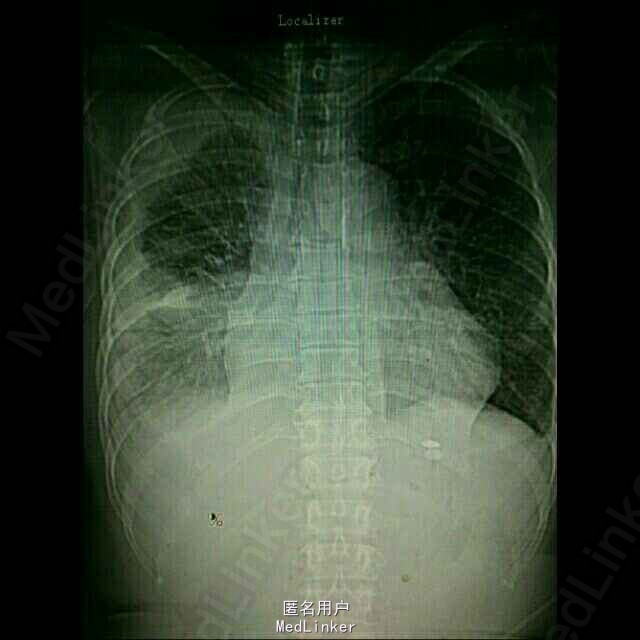

患者,女性,52岁。 2015年3月 因右侧胸腔积液,至外院就诊,胸水中找到腺癌细胞,胸部CT见右下肺占位。后多次胸腔闭式引流,但效果差。期间胸水脱落细胞检测EGFR,有突变,故口服靶向药物,并国产培美化疗一次。最近又出现心包积液,致呼吸困难入院。

入院后予以胸水引流,复查ct,行心包穿刺引流,改善症状,加强营养,纠正低蛋白。情况稳定后,在全麻下行右侧胸腔持续热灌注化疗,术中胸腔镜见胸壁大量转移病灶,取部分组织送检EGFR。术后经密切观察治疗,度过热疗损伤急性期。症情平稳后出院。术后EGFR阴性。

术后一月复查胸部CT,右肺较前进一步好转,并行力比泰+顺铂化疗。目前继续后续治疗,计划力比泰长期维持。